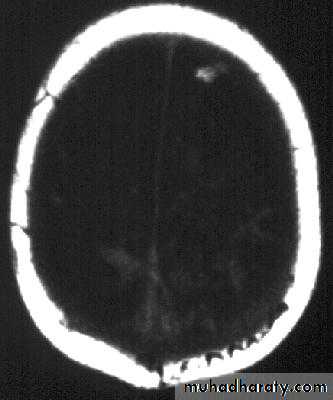

Bacterial Meningitis with suppuration

Neurosurgery